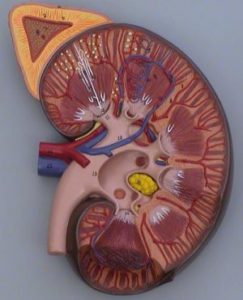

Андростерома — это опухоль, которая может быть как доброкачественной (аденома), так и злокачественной (карцинома). Определить ее характер возможно только после проведения гистологического анализа. Однако предварительно можно судить о природе новообразования по его размеру и массе. Эти параметры могут варьироваться в широких пределах — от нескольких миллиметров до 15-20 сантиметров и от нескольких граммов до 1-1,2 килограмма. Более крупные размеры (от 5 см) и большая масса обычно указывают на карциномы, которые могут давать метастазы в лимфатические узлы, расположенные рядом с почками, а также в печень и легкие. Такие опухоли могут состоять из одного крупного узла или представлять собой комбинацию нескольких узлов, объединенных в одно образование.

Малые андростеромы, как правило, являются доброкачественными. Это чаще всего одиночные опухолевые образования, имеющие круглую форму и светлый цвет, и их диаметр не превышает 5 см.

Увеличение андростеромы обусловлено повышенной выработкой ее тканью гормональных веществ, главным образом андрогенов из-за 1 или нескольких ферментных дефектов. Доброкачественное новообразование обычно неплотное, мягкой консистенции, заключенное в оболочку из соединительной ткани. Морфологически состоит из темных клеток, но сходных по строению с клетками, образующими сетчатую прослойку коры надпочечников. Они обычных размеров, компактные, с пузыревидными ядрами.

Клетки, образующие злокачественное новообразование, отличаются выраженным полиморфизмом, инфильтративным ростом, атипичностью, склонностью к некрозу. Андростерома и в этом случае обладает капсулой, но внутреннее содержимое у нее кистозно-измененное, красно-коричневого цвета, со множественными очагами некроза и мелких кровоизлияний.